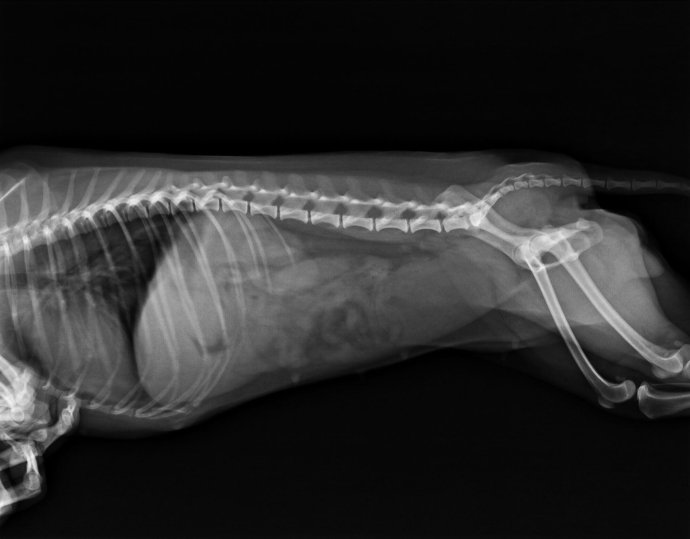

临床检查该犬精神沉郁,不愿动,触诊腹部的胃和小肠区敏感。结膜颜色粉红,体温39.5摄氏度。心音心率正常。怀疑胃肠道异物或胰腺炎,检查CBC/CPL,结果胰腺炎阴性,WBC 3.6*109/L,中性粒细胞数目降低,其他正常。拍CR平片如下:

第三天,又出现呕吐,精神较差,做CR检查,发现腹部胃内有一核状异物。但体外触诊不明显,但是胃部敏感。于是手术探查。

CR结果如下:

总结,在临床中,一些密度一般的异物不是很容易看出来,所以在临床中进行影像学检查是非常有必要的,特别是对一些有胃肠反应,触诊敏感,但无法触及异物的,必要的时候我们还需要对其进行造影检查。